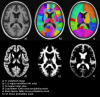

Mayo Clinic Adult Lifespan Template and Atlases